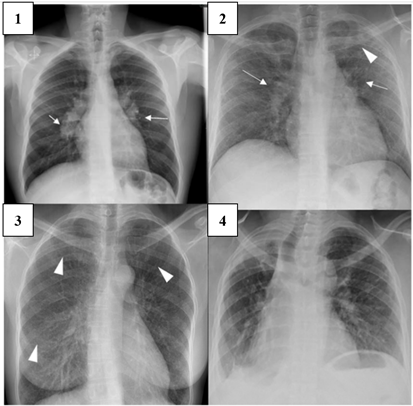

In the diagnosis of pulmonary sarcoidosis (PS), a special diagnostic method is computed tomography (CT), which is of significant prognostic value for the disease [6]. Mediastinal lymphadenopathy, particularly in the right paratracheal and aortopulmonary regions, is commonly observed in chest CT scans. The calcification of lymph nodes, alveolar and pseudoalveolar consolidations, and the "galaxy" sign are considered distinctive features of PS (Figure 2) [6].

/Nukusheva.files/image002.png)

Figure 2. Computed tomography images of patients with advanced pulmonary sarcoidosis and severe pulmonary dysfunction, candidates for lung transplantation